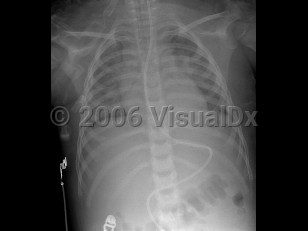

Smoke inhalation in Adult

The most common cause of death in fires is not thermal injury but rather the inhalation of noxious gases. Smoke is made of carbon dioxide, water vapor, carbon monoxide, fine particulate matter, hydrocarbons and other organics, and a variety of other substances. There may be many other toxic substances present in the smoke that increase when certain hazardous materials are burned, such as pressure-treated wood that may contain arsenic or chromate, insulation (including asbestos and fibrous materials), lead paint, particle board, asphalt (in roofing materials), used tires, rubber, plastics, vinyl materials, and foam padding (in mattresses and furniture).

Smoke inhalation can lead to many complications from irritation of the eyes and respiratory tract to acute and chronic lung disorders. The potential health problems will depend on what is being burned, concentrations of toxic substances in the smoke, the length of the exposure, and individual susceptibility (which will vary depending on the health of the individual and any medical problems they may have). The elderly, those with preexisting heart or lung conditions, smokers, and young children may be affected more severely by smoke inhalation.

Carbon monoxide (CO) poisoning frequently results from smoke inhalation. The acute presentation includes headache, dizziness, or nausea. Infants may present with vomiting. In patients with prolonged exposure, coma or seizures can occur, as well as altered mental status, retinal hemorrhages, lactic acidosis, and myonecrosis. Myocardial infarction may occur in the elderly, especially those with heart disease. Cherry-red skin color is associated with CO poisoning (2%-3%).